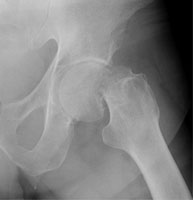

Femoral neck fractures also result from falls, especially in elderly and osteoporotic females. They are associated with radial and humeral fractures. The Garden classification is widely used to categorize these fractures. Garden I is an incomplete fracture through the femoral neck while with Garden II, the fracture is complete. With Garden III fractures, there is impaction, and with Garden IV, the femoral neck is superiorly migrated relative to the femoral head. Garden IV fractures have the highest risk of avascular necrosis.

B | Lateral view of a Garden II fracture. |